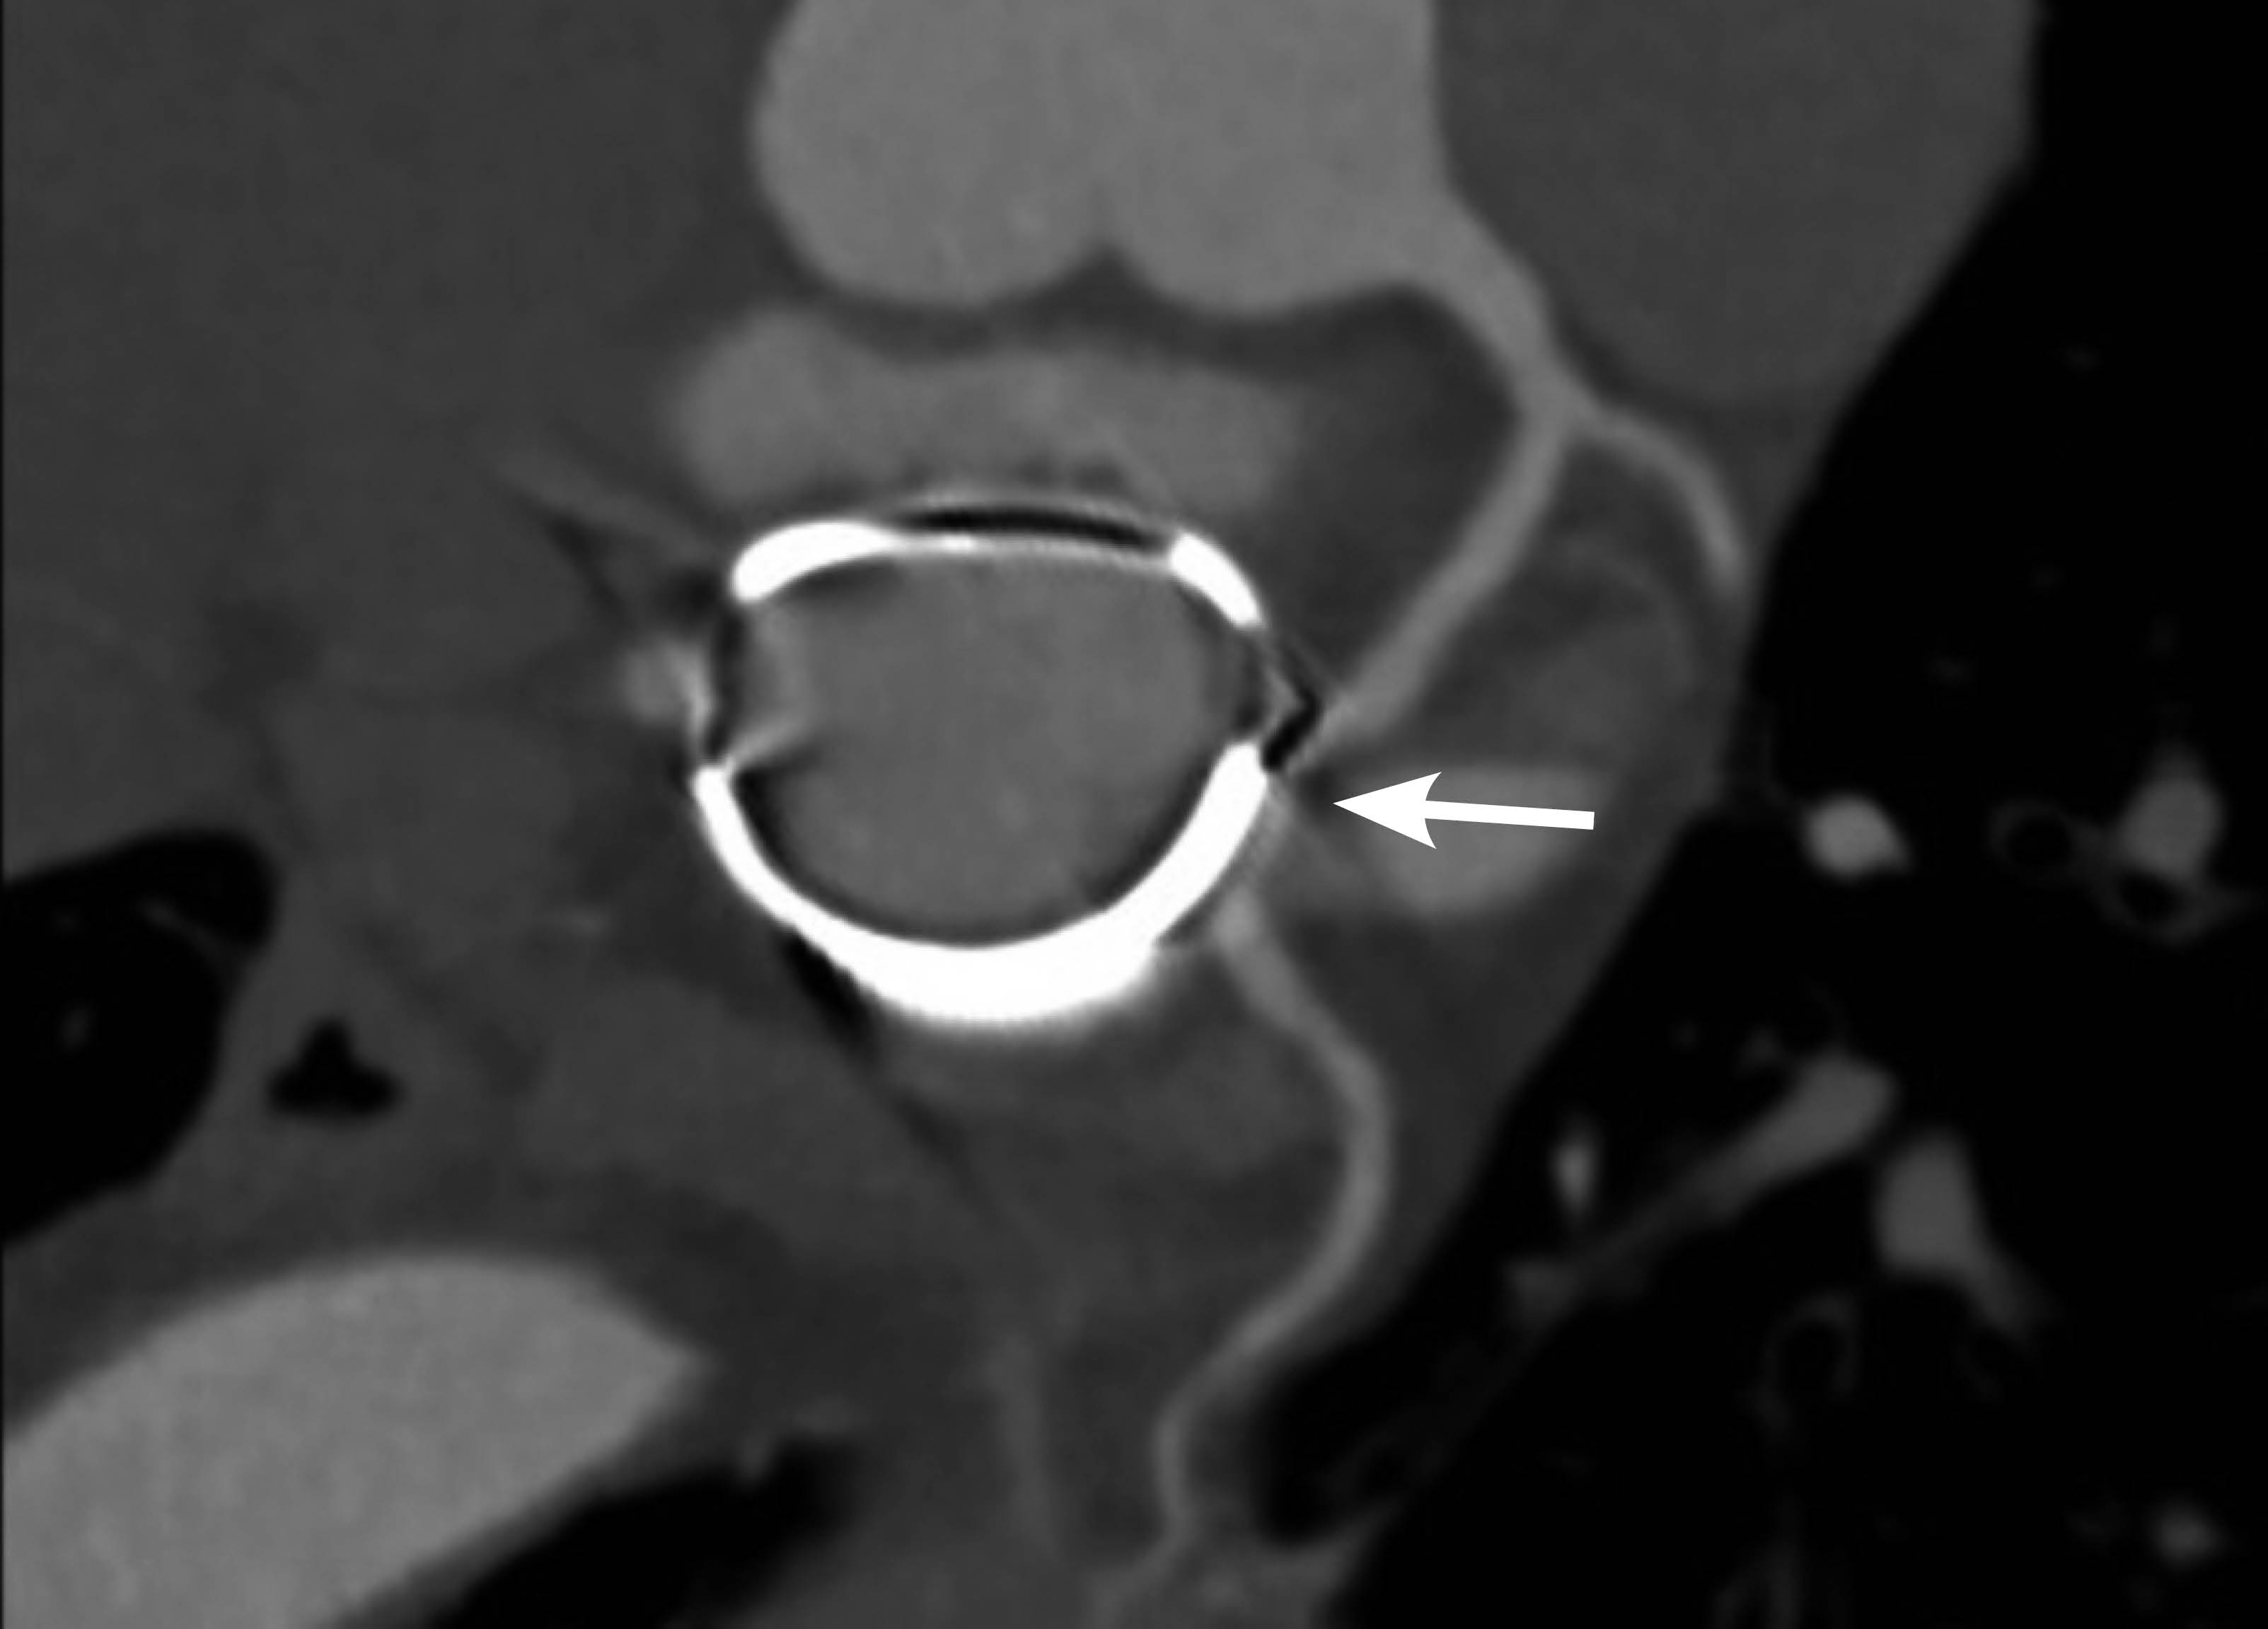

Introducción: las complicaciones agudas son frecuentes tras una sustitución o anuloplastia de la Válvula Mitral (VM). La isquemia inducida por la estenosis de la Arteria Circunfleja (ACx) causada por las suturas de la anuloplastia de la VM es la complicación aguda más frecuente. Presentación del caso: una mujer de 69 años con anuloplastia de la VM realizada con éxito cinco años previos se presentó con una historia de cuatro meses de dolor precordial opresivo al esfuerzo. Un ecocardiograma de esfuerzo mostró isquemia e hipocinesia de la pared inferolateral. La angiografía coronaria por tomografía computarizada reveló estenosis extrínseca en el tercio medio de la ACx, cerca del anillo de anuloplastia, en consonancia con los hallazgos de la angiografía coronaria. La resonancia magnética cardiaca demostró hipocinesia de la pared inferolateral y necrosis transmural de la pared inferolateral basal. Se realizó intervención coronaria percutánea con Ultrasonido Intravascular (IVUS) que mostró la estenosis. Realizamos angioplastia y colocación de stent con IVUS post-stent que mostró una adecuada aposición. El paciente fue dado de alta dos días después con tratamiento médico óptimo. La estenosis crónica de la ACx tras anuloplastia de la VM es extremadamente rara, con sólo cuatro casos descritos en la literatura. Conclusión: un enfoque multimodal, que incluye el uso de IVUS, puede ayudar a identificar el mecanismo de isquemia de una oclusión crónica de la ACx y en la toma de decisiones clínicas para un abordaje apropiado.

Figura 1